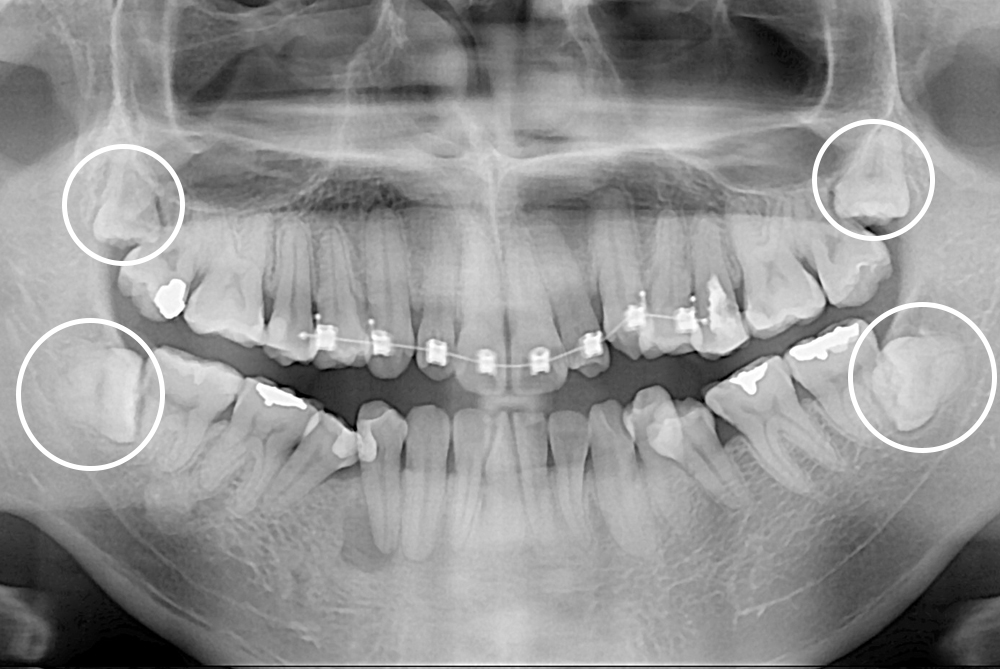

[사랑니] 매복 사랑니 발치

치료전 : 2018-02-07

세종치과는 구강악안면외과학 박사이신 원장님이 발치하는 치과입니다.